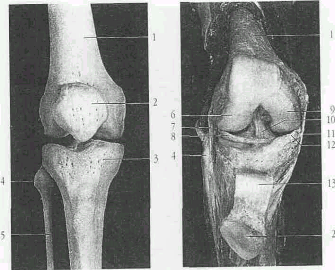

Рис 1. Строение колена.

Сустав колена - самый крупный сустав у человека. Он образован дистальным эпифизом бедренной кости и проксимальным эпифизом большеберцовой кости. По форме сустав колена относится к блоковидным суставам. Суставной конец бедренной кости состоит из двух мыщелков выпуклой формы. Суставная поверхность большеберцовой кости вогнутая. Однако несоответствие суставных поверхностей компенсируется наличием межсуставных хрящей - дисков. Медиальный мениск С-образной формы, а боковой - 0-образной. Мениски своими передними и задними рогами прикрепляются около мыщелковой возвышенности

Кроме того, передние рога соединены между собой поперечной связкой колена, а боковые поверхности - с капсулой сустава. Кроме крестообразных связок и менисков, сустав колена укреплен спереди сухожилием четырехглавой мышцы, которые ниже надколенника называют связкой надколенника. Часть пучков сухожильных волокон четырехглавой мышцы, идущих по боковым краям надколенника, прикрепляются к мыщелкам большеберцовой кости - медиальная и боковая поддерживающие связки надколенника. С боков сустав; колена укреплен двумя боковыми связками. Малоберцовая окольная связка начинается от бокового намыщелка бедра и прикрепляется к латеральной поверхности головки малоберцовой кости. Большеберцовая окольная связка начинается от медиального надмыщелка бедра, на уровне суставной щели срастается с капсулой сустава и медиальным мениском и прикрепляется к верхнемедиальной части большеберцовой кости. Разгибание в суставе колена осуществляется четырехглавой мышцей бедра, а сгибание - двуглавой мышцей бедра, полусухожильной и полуперепончатой мышцами.

Рис.2 Костные элементы коленного сустава. Правый коленный сустав.

1 - бедренная кость;

2 - надколенник;

3 - большеберцовая кость;

4 - головка малоберцовой кости;

5 - малоберцовая кость;

6 - боковой (латеральный) мыщелок.;

7 - наружная боковая связка коленного сустава;

8 - латеральный мениск (межсуставной хрящ коленного сустава);

9 - медиальный мыщелок коленного сустава;

10 - передняя крестовидная связка;

11 - внутренняя боковая связка коленного сустава;

12 - внутренний мениск (промежуточный диск коленного сустава;

13 - связка надколенника.

Внутри сустава расположены две мощные крестообразные связки колена. Капсула начинается в виде дуги на 0,5-1 см выше края хрящевой поверхности бедра, образуя впереди верхний заворот, переходит через сустав и прикрепляется к менискам, образуя боковые завороты. Спускается вниз и прикрепляется к большеберцовой кости, образуя передненижний заворот. Сзади капсула начинается по краю суставных поверхностей мыщелков бедренной кости, срастается с менисками и прикрепляется к краю суставной поверхности большеберцовой кости. На задней поверхности образуются задневерхний, задненижний, латеральный и медиальный завороты. Внутренняя поверхность капсулы выстлана синовиальным слоем, который с обеих сторон надколенника образует синовиальные крыловидные складки, включающие жировую клетчатку.